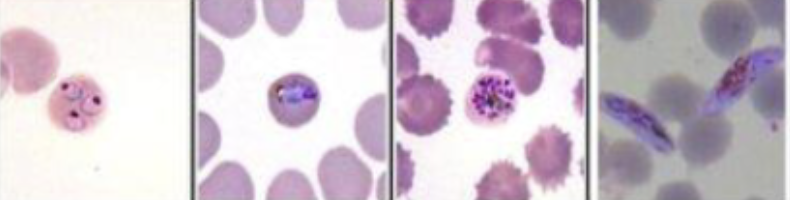

What malaria parasite is this?

Plasmodium falciparum

What parasite is this?

Plasmodium vivax

First stage of Malaria

Ring stage

Second stage Malaria

trophozoite

Third phase Malaria

Schizont

Fourth stage malaria

Gametocyte